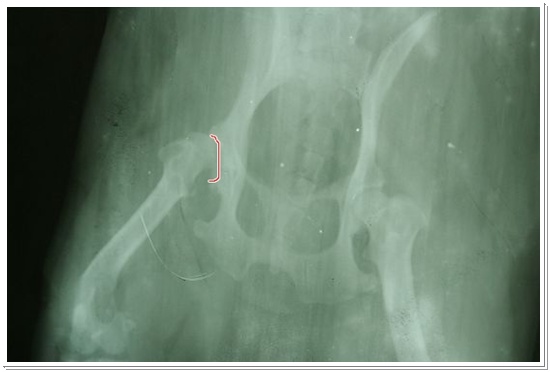

周醫生說這X光片雖然拍的不是很好,看出來江GO天生就有髖關節的問題,程度屬於中下...不用重照!

周醫師說,韌帶有分很多種,股骨頭和髖臼之間有個「圓韌帶」,是穩定股骨頭的作用,

通常髖關節異位不正常,這個圓韌帶一定是會斷的...不過,並不會有多大的影響...